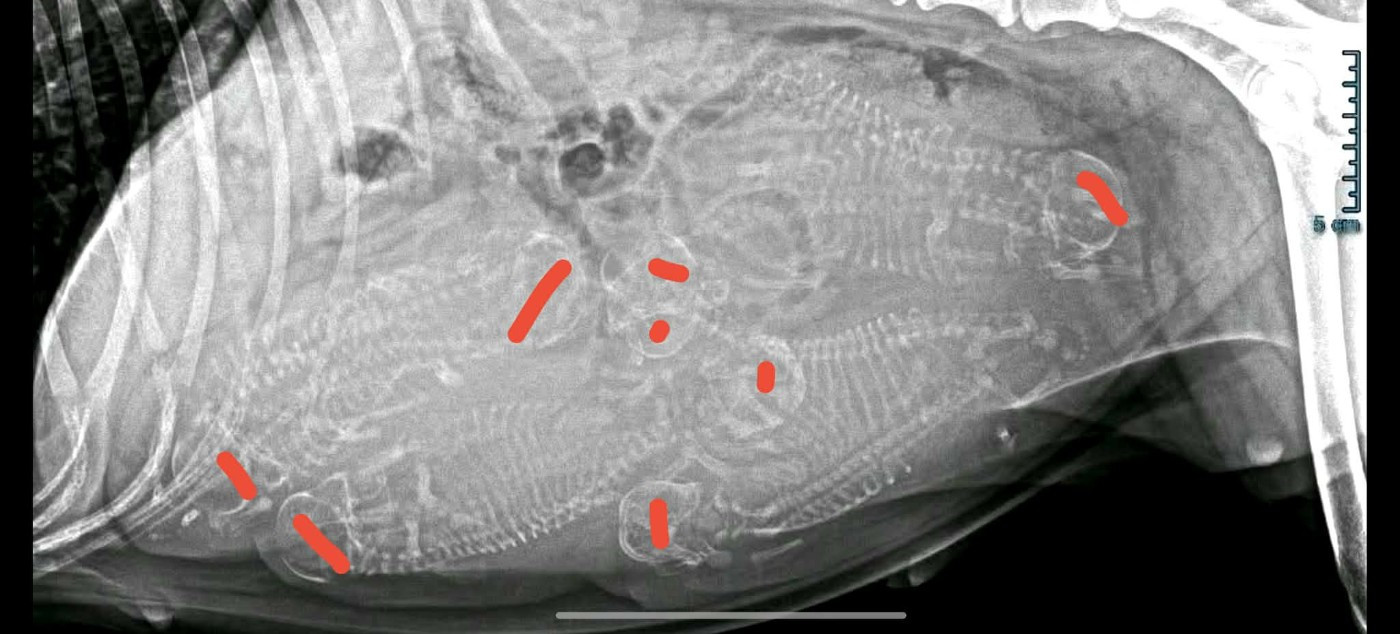

Alors à votre avis combien de bb se cachent dans mon ventre ?

La radio de gestation faite ce mercredi 25 février nous avons montré 8 petits crânes...